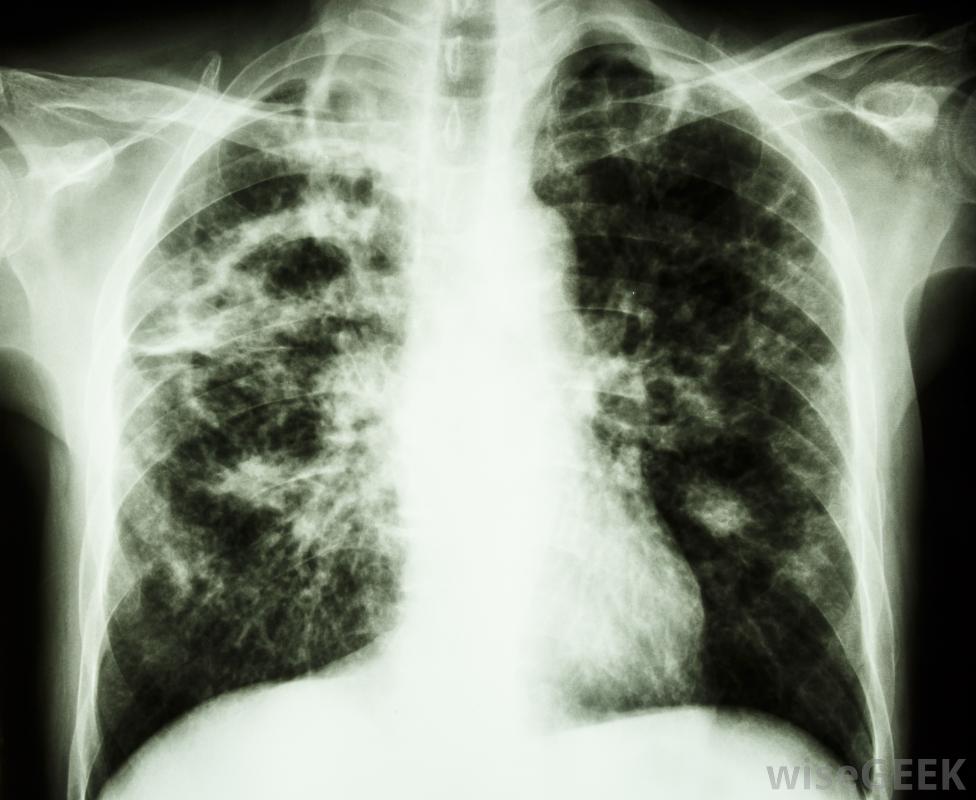

卡介苗(BCG)是结核病高发国家常用的一种结核病疫苗。疫苗是由与引起结核病的细菌相似的少量活菌制成的。接种卡介苗后感染结核病的人通常会很好很快,因为疫苗能阻止结核杆菌在体内传播。

卡介苗自1921年开始使用,对控制结核病非常有效研究各不相同,但大多数研究表明,在56%到80%之间的有效性,并且当给幼儿接种时可能高达100%。有不同类型的卡介苗疫苗,它们来自不同的牛分枝杆菌菌株。

结核病检测呈阴性且生活在经常接触结核病的地区的儿童应接种卡介苗。这对于异烟肼-抗利福平肺结核很常见。如果医护人员持续接触结核病并有可能被感染,他们可能需要接种疫苗。